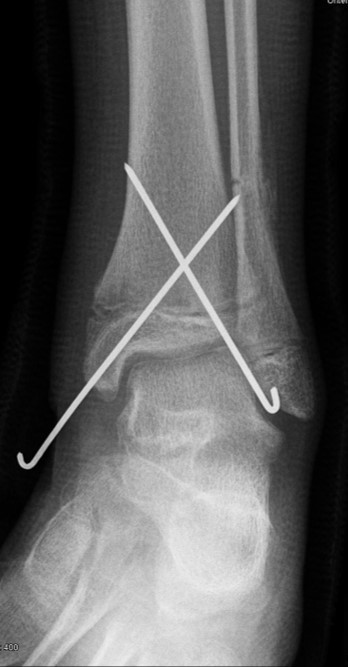

Findet sich eine Dislokation der Wachstumsfuge erfolgt nach Reposition eine K-Drahtspickung. Die postoperativ angelegte Gipsschale wird nach Abschwellung entfernt und ein Unterschenkelgips für 4 Wochen angelegt.

Nach Gipsabnahme können die Drähte entfernt und das Sprunggelenk zunehmend aufbelastet werden.